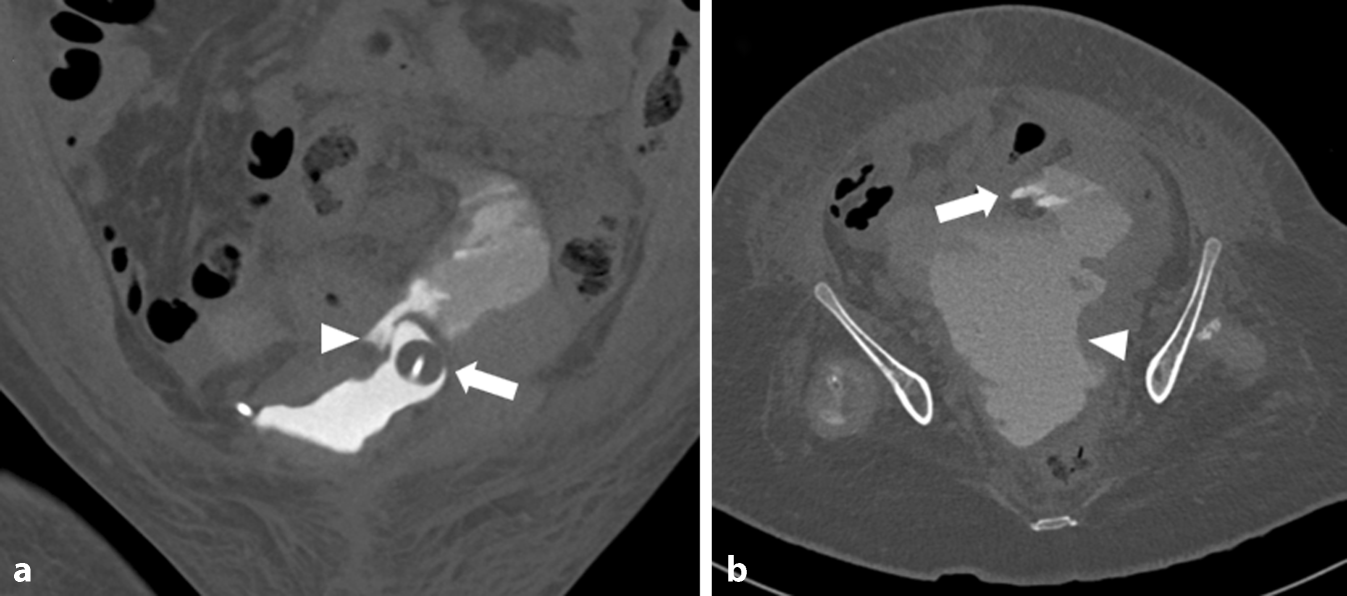

Abb. 2

Computertomographie (CT) des Abdomens in urographischer Phase in a koronarer und b axialer Rekonstruktion (Knochenfenster). a Zwischenzeitlich wurde ein Harnblasenkatheter über die Ausleitung im rechten Unterbauch eingebracht. Der geblockte Ballon liegt im Divertikel (Pfeil). Zudem Nachweis von austretendem Kontrastmittel/Urin (Pfeilspitze). b Abzugrenzen ist das austretende Kontrastmittel/Urin mit Ausbildung eines großen Urinoms im Unterbauch (Pfeilspitze)